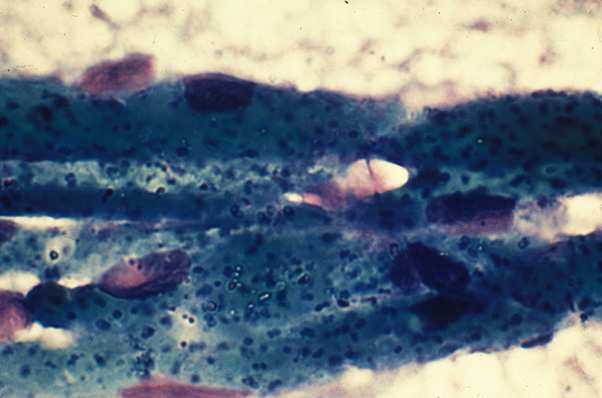

Cerebral babesiosis due to Babesia bovis. Brain smear showing numerous parasites in the red blood cells